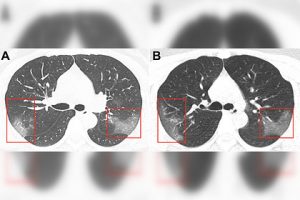

Сейчас Бабкина находится в искусственной коме и подключена к аппарату искусственной вентиляции легких.